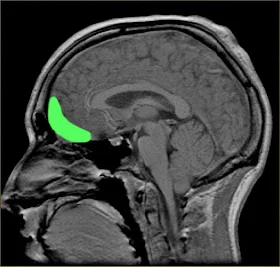

وتقول الدكتورة Dr Valerie Voon لقد وجدنا نشاطاً هائلاً في منطقة في الدماغ تدعى ventral striatum وهي المنطقة المسؤولة عن المكافأة والتحفيز والسعادة (المرجع رقم 1).

تظهر الصور الناتج عن المسح المغنطيسي أن المنطقة المسؤولة عن المكافأة في الدماغ تنشط بشكل غير عادي أثناء رؤية المشاهد الخلاعية، وإن تكرار هذه المشاهد يؤثر على الدماغ وينهكه تماماً بنفس تأثير المخدرات والخمر (المرجع رقم 3).

تظهر الصور بالمسح بالرنين المغنطيسي أن المنطقة الأمامية تتآكل وتتضرر كثيراً بنتيجة الإدمان على مشاهدة المناظر الجنسية. (المرجع 12). هذه المنطقة عندما تفقد جزءاً منها فإن سلوك الإنسان يضطرب ويفقد توازنه وينقاد وراء شهواته كالمجنون.. وقد ينتحر أو يرتكب جرائم... (المرجع 23).